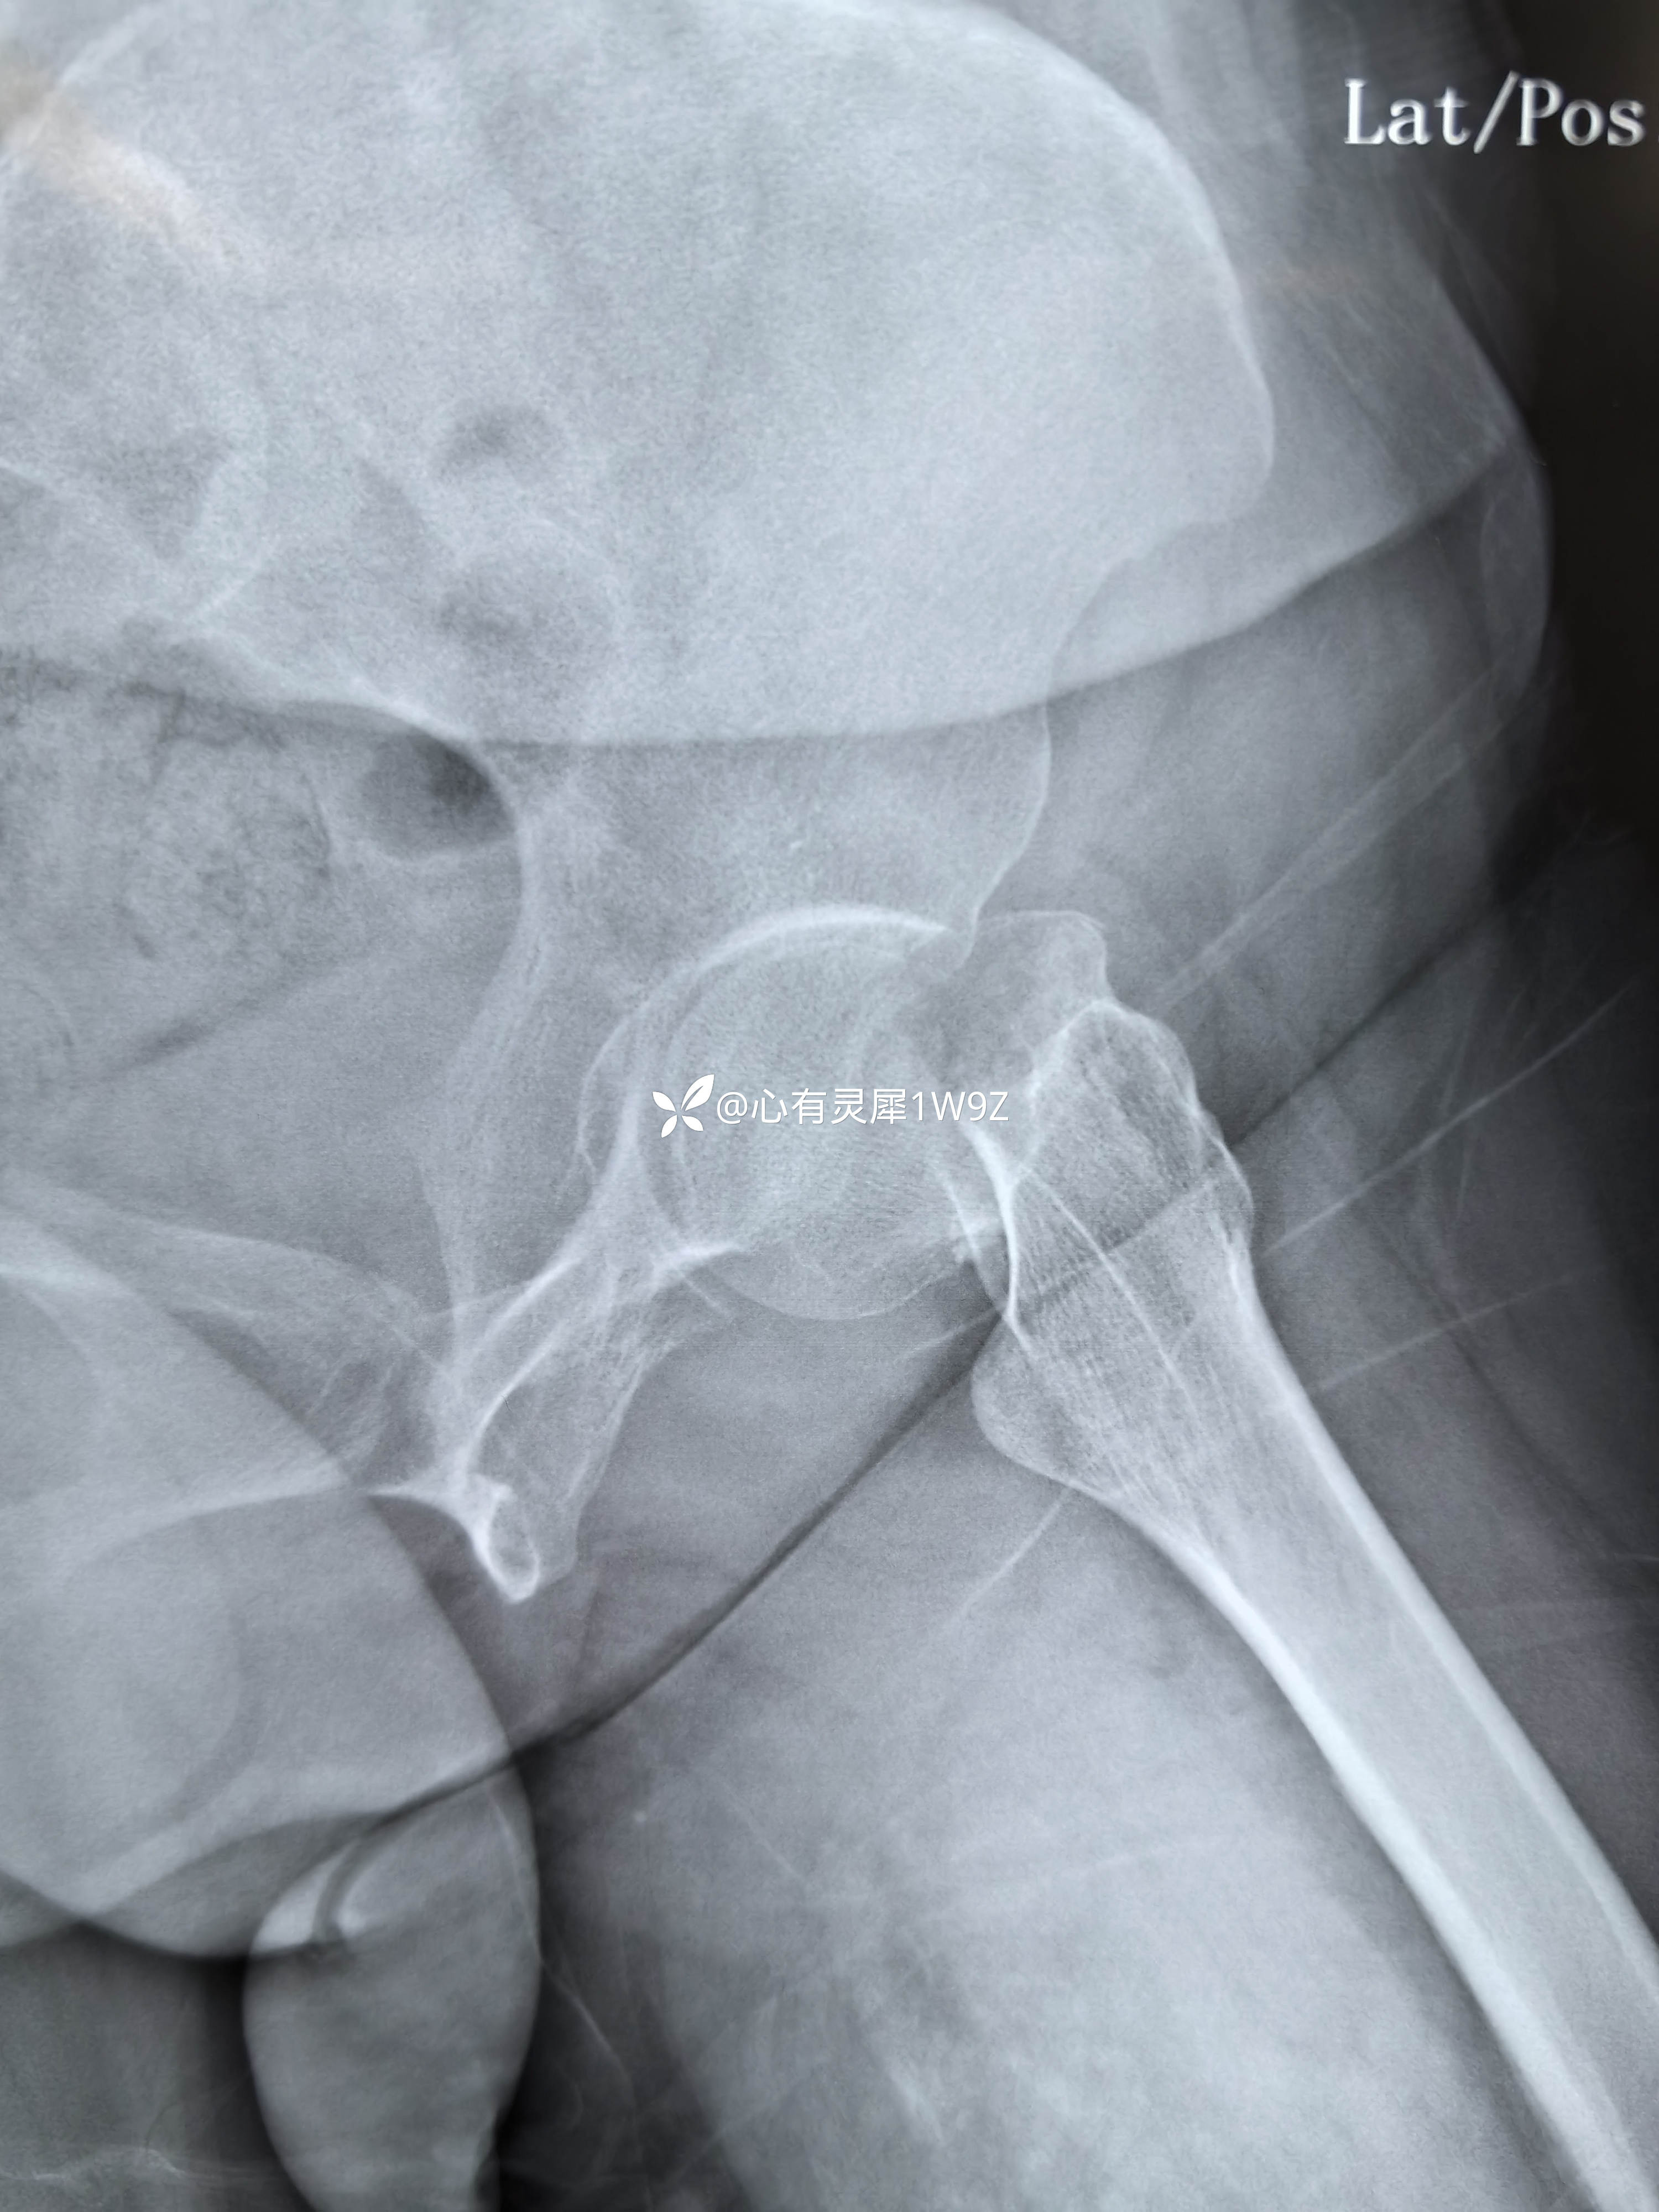

诊断:左侧股骨颈骨折(头下型)garden IV型

向患者及家属讲解治疗方案。患者和家属选择做内固定。积极准备后在24小时内手术。椎管麻醉,手术顺利,计划首先闭合复位,复位失败就切开复位,三枚加压空心钉固定。

2,关于贴壁,平行,长度,角度。自己感觉这次平行和长度都比较满意,贴壁还可以,角度不是很完美,感觉可以接受,就没有再调整。